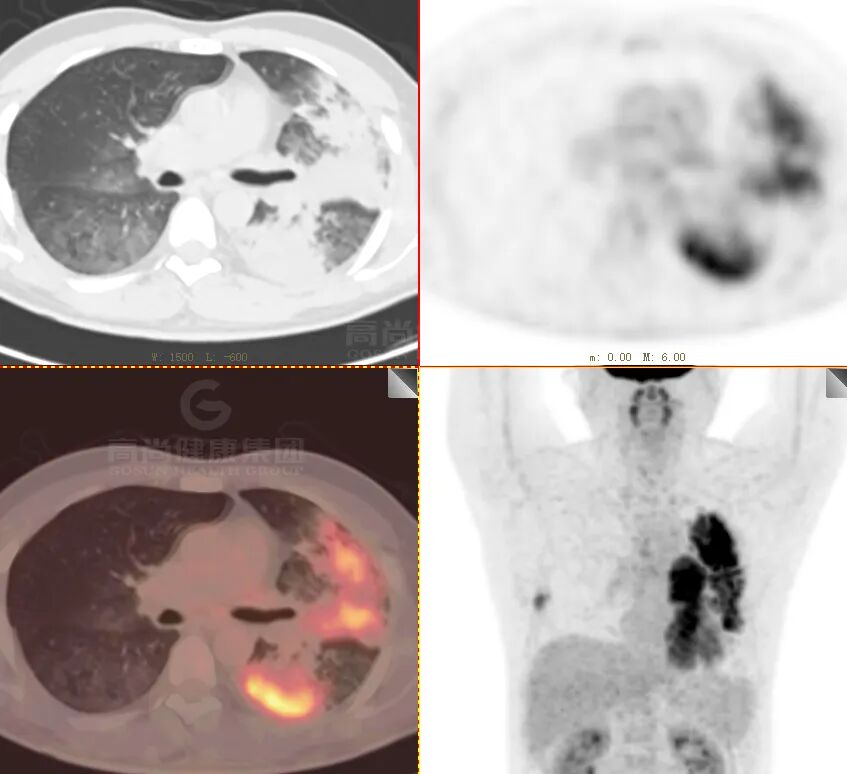

PET/CT 图像

PET/CT 表现

双肺多发斑片状实变影,内充气支气管征,部分囊状扩张,FDG 摄取不均匀增高,SUVmax5.1

右下肺病灶穿刺病理

黏膜相关淋巴组织结外边缘区淋巴瘤(MALT 淋巴瘤)